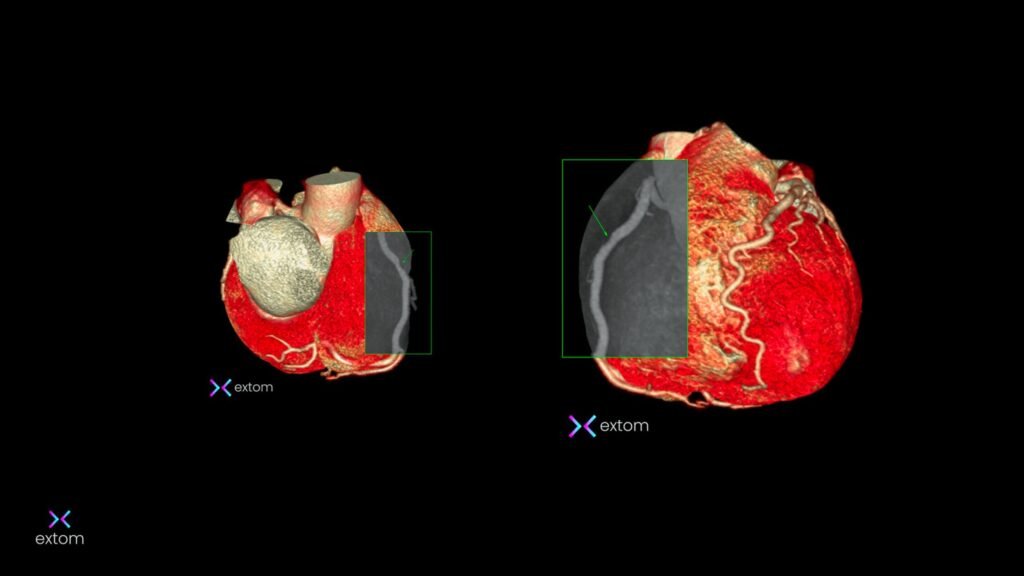

EXTOM fue fundada con un propósito claro: ofrecer estudios de alta precisión para contribuir al bienestar de los pacientes . Desde nuestros inicios, marcamos un antes y un después en la región con la adquisición de un tomógrafo de 128 detectores, optimizando la detección temprana de enfermedades complejas .

A lo largo de nuestra trayectoria, hemos sido pioneros en técnicas avanzadas de imagen cardíaca y procedimientos intervencionistas que evitan cirugías innecesarias . Hoy, con la incorporación de la resonancia magnética de 1.5 Teslas, reafirmamos nuestro compromiso de ser el aliado principal de los médicos y pacientes en Loja .